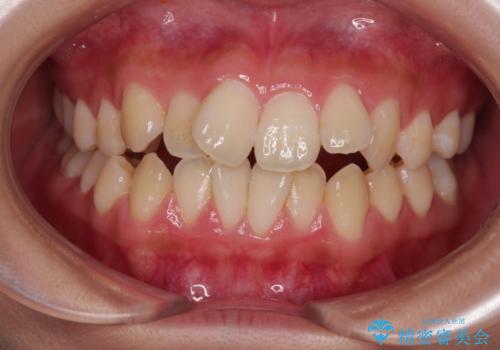

[セラミック治療] 前歯の審美治療に伴う矯正治療